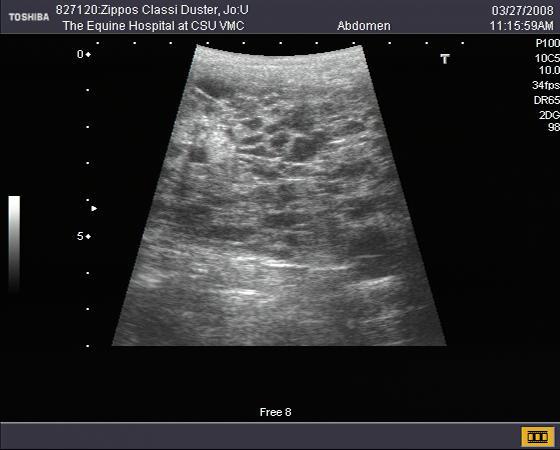

A transrectal ultrasound examination was subsequently performed. The left ovary was determined to be enlarged (approximately 10 cm in diameter) and contained numerous cystic pockets (Figure 1). The contralateral right ovary was small and exhibited limited follicular development (Figure 2). Examination of the uterus indicated that the mare was not pregnant.

Figure 1. Ultrasound image of the enlarged left ovary

(bracket). Note the multi-cystic appearance of the ovary

(arrow).